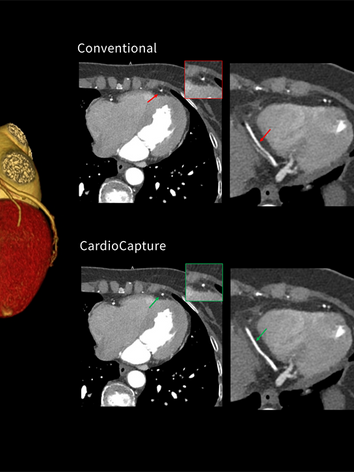

Improved image quality for challenging patients with cardiac excellence